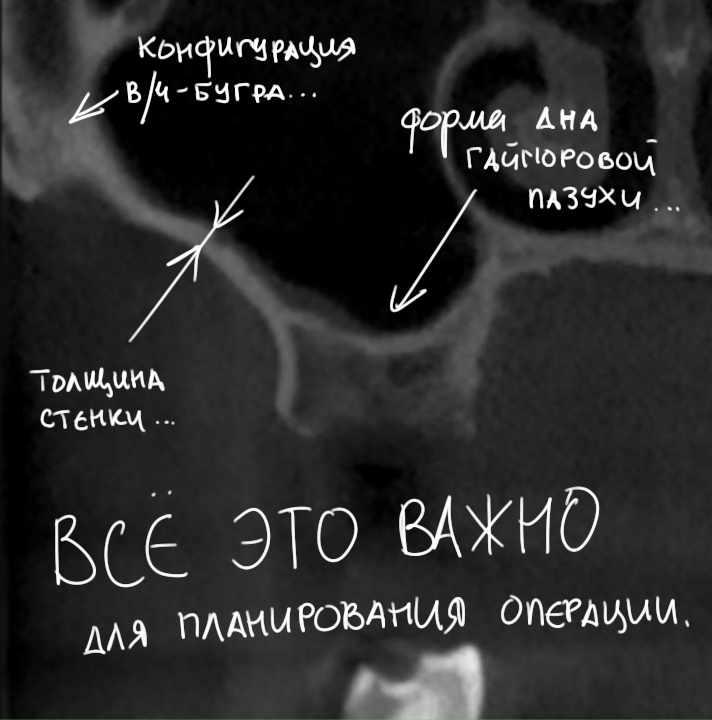

Ортопантомография подразумевает «перенос» трехмерной структуры в двухмерную проекцию, поэтому в ней неизбежны искажения. Планировать операцию по ортопантомограмме мы можем лишь приблизительно, буквально в пределах понятий «нужен синуслифтинг или нет».

По ортопантомограмме невозможно понять толщину стенок верхнечелюстной полости, их конфигурацию в щечно-небном направлении, нельзя определить, как соотносятся корни зубов с дном верхнечелюстной пазухи. А это, в свою очередь, очень важно при планировании операции синуслифтинга (рис 14).

Рисунок 14. Многие нюансы, важные при планировании операции синуслифтинга, просто не видны на ортопантомограмме.

Золотым стандартом в обследовании пациентов, которым планируется операция синуслифтинга, является проведение конусно-лучевой компьютерной томографии. Анализируюя ее, можно не только определить пространственную конфигурацию верхнечелюстной пазухи, но и выявить анатомические структуры, которые могут повлиять на ход оперативного вмешательства. Более того, современные программы КЛКТ позволяют оценить состояние слизистой оболочки гайморовой пазухи.

Нужно ли говорить, что это всё это является важным при планировании операции синуслифтинга?